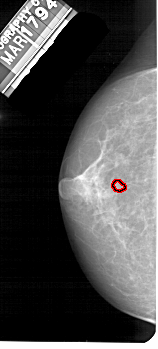

A_1545_1.RIGHT_MLO

RIGHT_MLO LINES 5221 PIXELS_PER_LINE 2416 BITS_PER_PIXEL 12 RESOLUTION 43.5 NON_OVERLAY

FILE: A_1545_1.LEFT_MLO.OVERLAY

TOTAL_ABNORMALITIES 1

ABNORMALITY 1

LESION_TYPE MASS SHAPE LOBULATED MARGINS OBSCURED

ASSESSMENT 4

SUBTLETY 2

PATHOLOGY BENIGN

TOTAL_OUTLINES 1